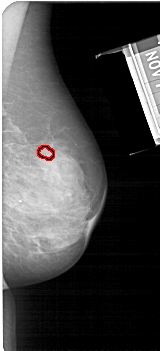

FILE: A_1683_1.RIGHT_MLO.OVERLAY

TOTAL_ABNORMALITIES 1

ABNORMALITY 1

LESION_TYPE MASS SHAPE OVAL MARGINS OBSCURED

ASSESSMENT 3

SUBTLETY 3

PATHOLOGY BENIGN

TOTAL_OUTLINES 1

BOUNDARY